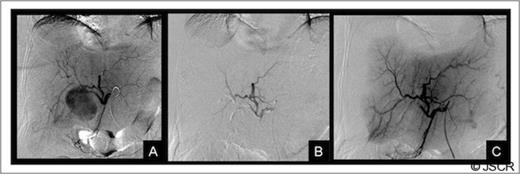

Forty-eight hours after admission the patient had an episode of haemodynamic instability suggestive of septic shock, which was also associated with a drop of 15 points in haematocrit levels (haematocrit: 24, WBC: 33 000). Empirical antibiotic therapy was begun and abdominal contrast-enhanced computed tomography (CT) was performed. CT showed a pseudoaneurysm of the right hepatic artery (RHA) of 7 cm in diameter, haemoperitoneum, intrahepatic dilatation of the biliary tree bile duct and the presence of hepatic infarction, and duodenal wall involvement (Figures 1 and 2).

CT of the abdomen: A) Tridimensional reconstruction, B) Axial slice C) Coronal slice (a;.Pseudoaneurysm of the right anterior hepatic artery, b;Left hepatic artery, c;Common hepatic artery, d;Gastroduodenal artery). The right posterior hepatic artery arises from the left hepatic artery.

CT of the abdomen: Complications of the pseudoaneurysm A, B) Hepatic infarction C)Duodenal wall involvement, D) Hemoperitoneum under right hemidiaphragm.